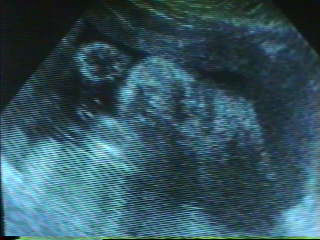

| He’s Getting Cuter Every Day! |

| This week we got to see our un-born son’s face. Below are 2 views of his face and a diagram to help you figure out the pictures. The coolest thing was that we could see him sucking on his thumb. His little cheeks were moving in and out. Only 11 more weeks to go. |